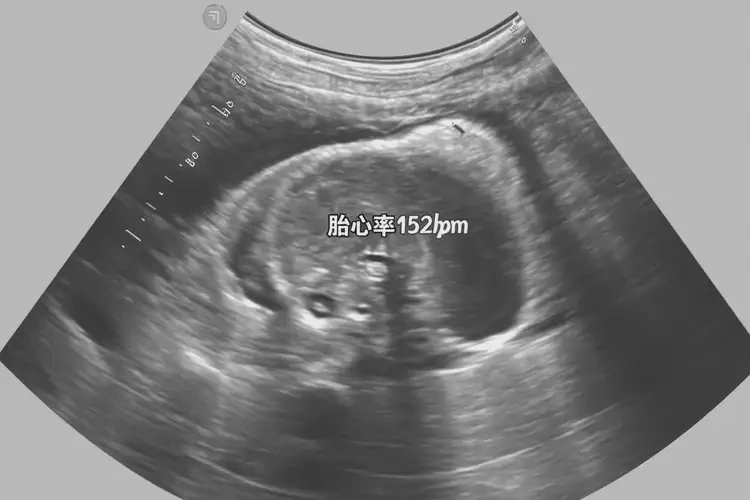

懷孕26周胎心152正常嗎(圖2)

三、胎心監(jiān)測(cè)的方法

1. 多普勒超聲:多普勒超聲是一種常用的胎心監(jiān)測(cè)方法。通過將超聲探頭放置在孕婦的腹部,醫(yī)生可以實(shí)時(shí)監(jiān)測(cè)胎兒的心臟跳動(dòng)情況。